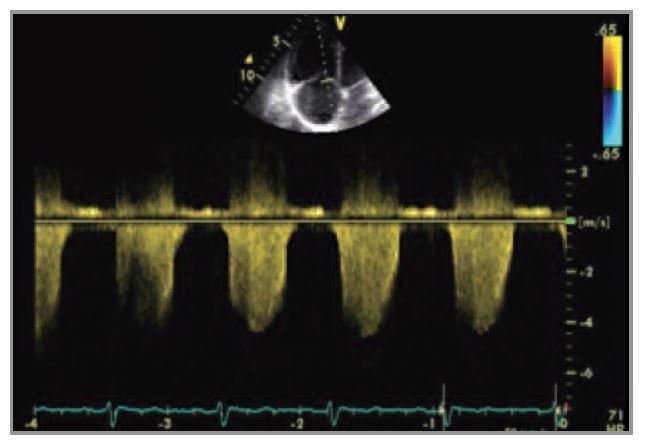

- По данным допплер-ЭхоКГ выявлены ЭхоКГ-признаки ЛГ: СДЛА – не менее 80–85 мм рт. ст.; дилатация правых отделов сердца; гипертрофия свободной стенки ПЖ; трикуспидальная регургитация 2–3-й степени, индекс TAPSE 21–22 мм.

При контрольном ЭхоКГ-исследовании на фоне базисной и ЛАГ-специфической терапии определялись признаки ЛГ: дилатация правых отделов сердца, трикуспидальная регургитация 2-й степени, СДЛА около 60–65 мм рт. ст., однако по сравнению с предыдущим исследованием степень их выраженности стала меньше. Систолическая функция ПЖ не была снижена: TAPSE 23 мм. Существенных структурно-функциональных изменений левых отделов сердца не выявлено (см. рис. 4 на цветной вклейке).

Рис. 4 ЭхоКГ: дилатация правых отделов сердца, трикуспидальная регургитация (систолический градиент давления между ПЖ и правым предсердием равен 60-65 мм рт. ст.)